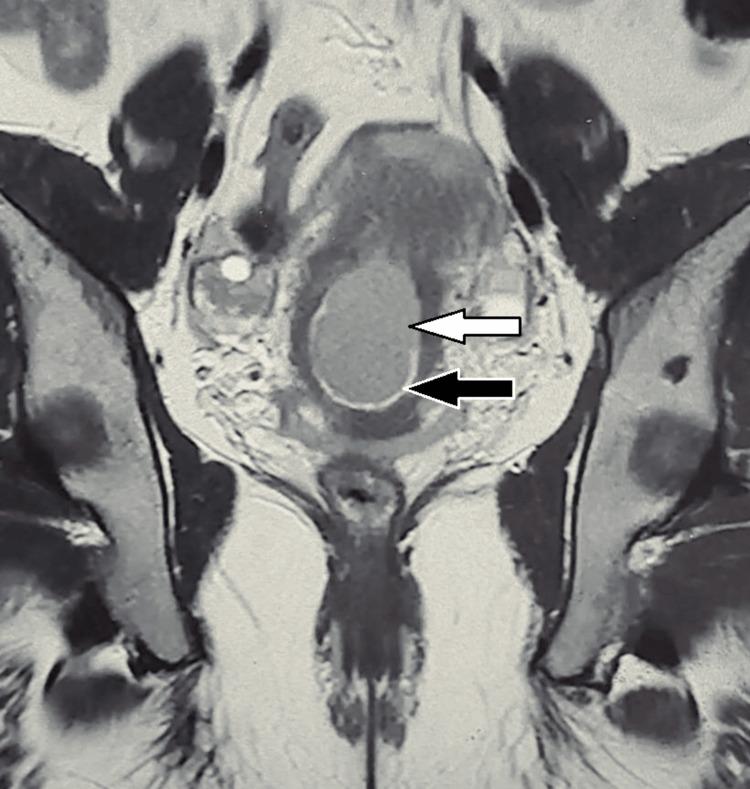

Osseous metaplasia of the endometrium is the presence of mature and immature bone tissue inside the endometrial cavity. We present a case series of three women who presented with various complaints of vaginal discharge and menstrual abnormalities. On hysteroscopy, bone fragments were extracted. Histopathological study of the bone tissue was supportive of osseous metaplasia. We performed a DNA analysis of the bone and compared it to the maternal genotype. We found a complete match between the patient and bone genotype, thus supporting that the bone originates from the patient.

https://cdn.ncbi.nlm.nih.gov/pmc/blobs/8ad3/11972108/0d29fc282e64/cureus-0017-00000080145-i01.jpg